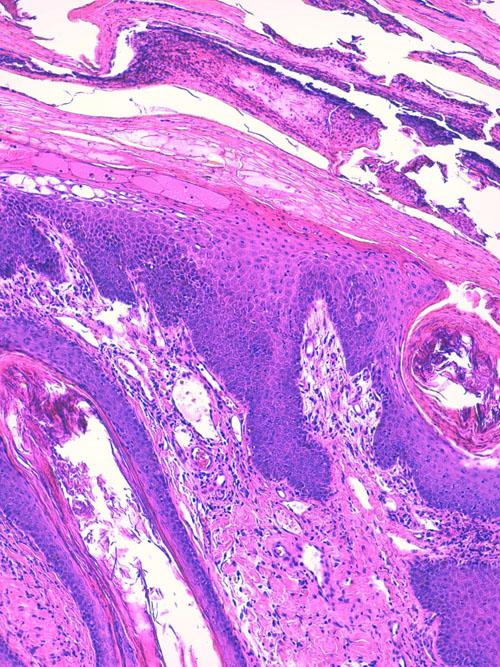

L’examen histologique (LAPVSO, Frédérique DEGORCE) décrit une hyperkératose parakératosique intense constituant une couche cornée épaisse et compacte. Des foyers d’acanthocytes vacuolisés et oedémateux sont présents avec scission de l’épiderme à leur niveau. Une exocytose transépidermique modérée de lymphocytes et neutrophiles est présente, sans images de satelllitose. Le derme est peu inflammatoire, oedémateux et congestionné. Sur certaines biopsies, les lésions ulcérées et vésico-pustuleuses prédominent au sein de la couche cornée. L’examen confirme l’hypothèse d’érythème nécrolytique migrant avec complication de pyodermite supeficielle impétiginée. (photos)

Photos 9 et 10 : Lésions cutanées